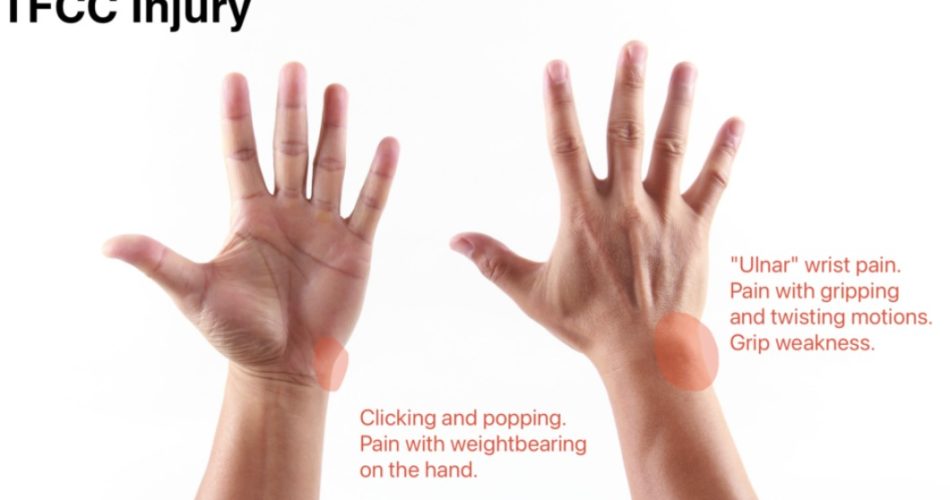

- Ulnar-sided wrist pain: Localised to the ulnar aspect of the wrist, aggravated by gripping, forearm rotation (particularly pronation with load), and impact activities

- DRUJ instability: A sensation of the ulnar head ‘clicking’ or ‘subluxing’ with forearm rotation — suggests disruption of the radioulnar ligaments

- The ‘piano key sign’: Abnormal dorsal subluxation of the distal ulna that reduces with passive pressure, like depressing a piano key — indicates DRUJ instability